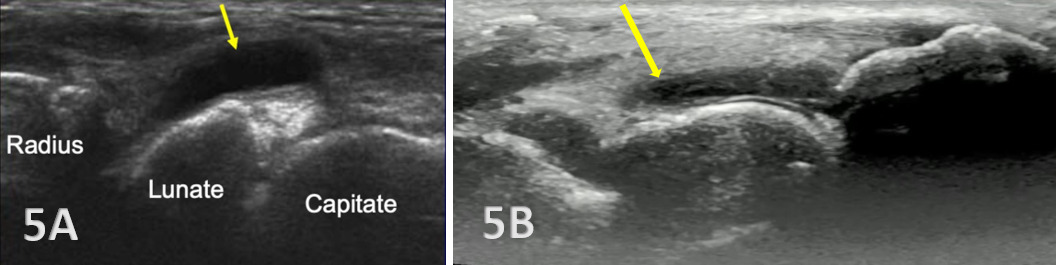

Hyperechoic irregularities of bone of the radius, scaphoid, and lunate are visible.

Hypoechoic bands of synovial tissue folds are present.

Anechoic or hypoechoic joint effusion and/or synovitis (synovial hypertrophy) and cysts within the joint.

Joint effusion is somewhat compressible and mobile when transducer pressure is applied to the area. This is different from synovitis, which appears as hypoechoic or isoechoic, non-compressible tissue within the joint recess. Synovitis may be associated with conditions such as rheumatoid arthritis, psoriatic arthritis, or other inflammatory arthropathies. Lastly, a ganglion cyst may appear as a well-defined, round or lobulated cystic structure with anechoic or hypoechoic internal contents. The cyst will usually have a small, smooth wall and exhibit posterior acoustic enhancement. These cysts will typically be minimally or non-compressible and painful.

Early Detection of Injury / Accurate Injury Grading: MSKUS can detect small anechoic or hypoechoic fluid collections in the radiocarpal recess that may be invisible to the naked eye. Finding this early will help guide treatment planning. Additionally, small ligament sprains or partial tears may be seen on ultrasound as irregular loss of normal fibrillar patterns.

Dynamic Functional Testing: Rehabilitation professionals can use MSKUS to dynamically stress the tissues with gentle wrist motion to reveal instability or soft tissue impingement between bones or abnormal findings such as cysts.